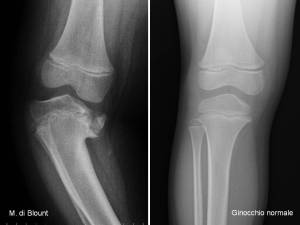

Morbo di Blount. E’ piuttosto raro: un caso ogni 3-4.000 ginocchia vare fra i 2 e i 5 anni. Quando insorge a questa età si parla di Blount infantile (fig 11).

E’ dovuto ad una sofferenza del versante interno della cartilagine di accrescimento prossimale della tibia (osteitis deformans tibiae, fig 12).

- Fig .12: RX morbo di Blount e ginocchio normale

Il femore non è interessato. E’ molto difficile, prima dei due anni, differenziare una tibia vara intraruotata infantile, accentuata ma banale, da un Blount debuttante. Bisogna sospettarlo in caso di unilateralità (anche se la malattia può essere bilaterale), di ostinato ritardo nella correzione spontanea e quando si palpa una sporgenza sulla metafisi tibiale interna. Una radiografia delle ginocchia in antero-posteriore (da eseguirsi ogni qual volta un varismo importante persiste oltre i 3 anni) chiarirà il quadro, mostrando il caratteristico “becco metafisario” (fig 12), l’iposviluppo della porzione mediale dell’epifisi, la sofferenza della cartilagine di accrescimento dello stesso lato. La terapia è chirurgica mediante osteotomia di sollevamento dell’emipiatto tibiale mediale, fig 13-14). Si può dilazionare l’intervento fino ai quattro anni, applicando calzature correttive con piano inclinato laterale, ma non oltre, per non correre il rischio di un progressivo ed irreversibile deterioramento della cartilagine coniugale mediale della tibia, causa di sicura recidiva della deformità.